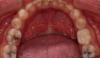

Пациент, 15 лет. Зуб 75, зачаток 35 отсутствует.

Нормализация окклюзии при анкилозе молочного зуба композитной реставрацией

Композитная реставрация с помощью материалов: SDR, Дентин Ceram-X Duo D2, эмаль Estelite Sigma Quick.

Полировка Enhance + Opti1step, диски ТОР.

Фотоотчет работы